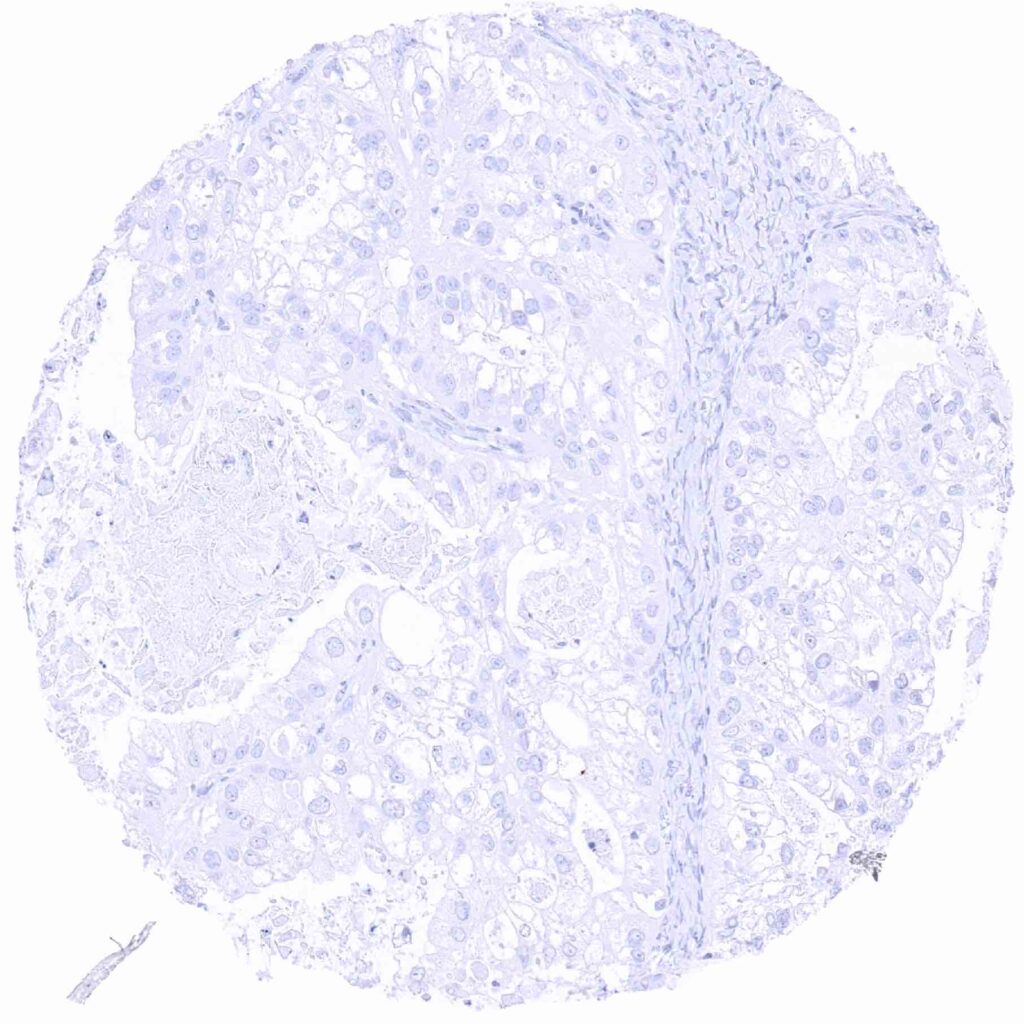

Kidney – Prostein negative clear cell carcinoma